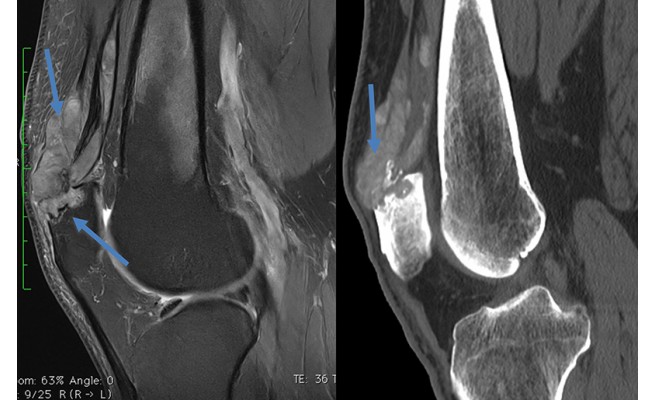

Tophus goutteux / Hyperurcémie chronique

La goutte est l'expression ostéo-articulaire d'une hyperuricémie, conséquence d'une production excessive ou d'un défaut d'élimination de l'acide urique. Elle se caractérise par des épisodes récurrents d'arthrite aiguë.